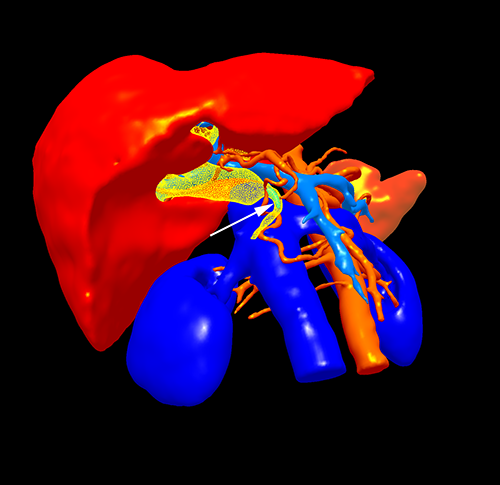

胆总管下端癌--胰十二指肠切除